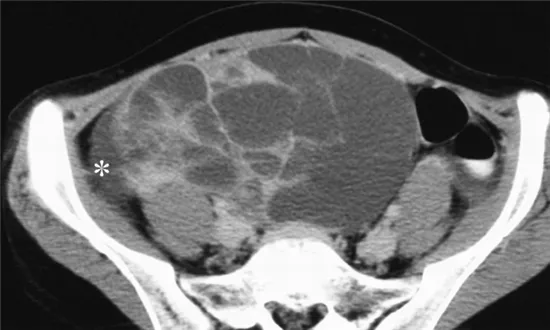

72세 여성이 복부 불편감과 지속적인 체중 증가를 호소하며 병원을 방문했다. 복부 초음파 검사에서 다량의 복수가 발견되었고, 복수 천자 세포학적 검사에서 악성 세포가 확인되었다. 복부 CT 스캔에서 난소 종양이 의심되는 소견이 관찰되었다. 아래는 환자의 혈액 검사 결과이다. 적절한 치료 방법은 무엇인가?

• 복부팽만감, 체중증가를 호소하는 여성 환자에서 복수가 관찰되었다. 복수검사 상 악성세포의 확인, 복부 CT 상 난소 종양, CA-125 상승을 바탕으로 난소암을 강력히 의심할 수 있다.

• 영상 및 지문에서 수술이 불가능하거나 upfront debulking이 실패할 것으로 예상되는 소견은 보이지 않으며, 전신 상태(ECOG) 저하 언급도 없다.

• 따라서 난소암의 표준 치료 원칙에 따라 탐색적 개복술을 통해 일차 감축수술(Primary Debulking Surgery, PDS) 을 먼저 시행해야 하며, 이는 병기 결정(staging)과 종양 감축(debulking)을 동시에 수행하게 된다.